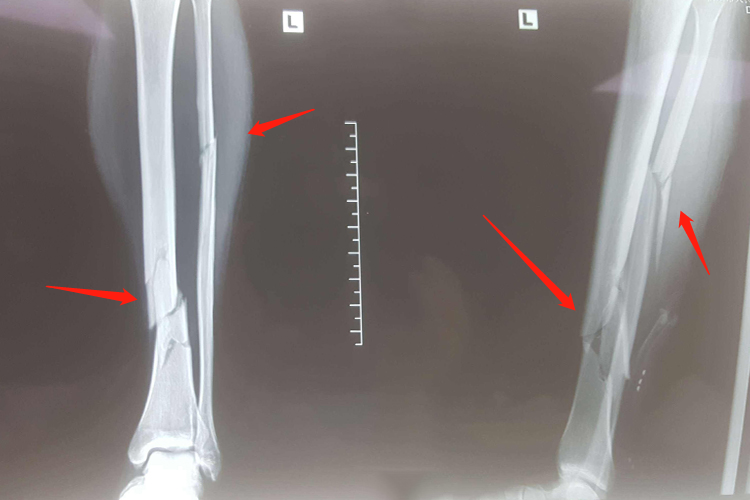

胫骨骨折畸形愈合:是指骨折断端在重叠、旋转、成角状态下连接,而引起肢体功能障碍。X线上显示胫骨骨折端产生的骨痂较少、骨折线不消失、骨折断端无硬化现象,且有轻度脱钙。

胫骨骨折迟缓愈合:胫骨骨折经治疗后,已超过同类骨折正常愈合的最长期限,骨折处局部仍有肿胀、压痛,纵轴叩击痛,异常活动,功能障碍。X线片显示骨痂生长缓慢而未连接,但骨折断端无硬化现象,骨髓腔仍通。

胫骨骨折不愈合:是指胫骨骨折愈合功能停止,骨折端已形成假关节。X线片显示胫骨骨折端互相分离,间隙增大,骨端硬化或萎缩疏松、髓腔封闭,用一般的固定方法无法使之连接。